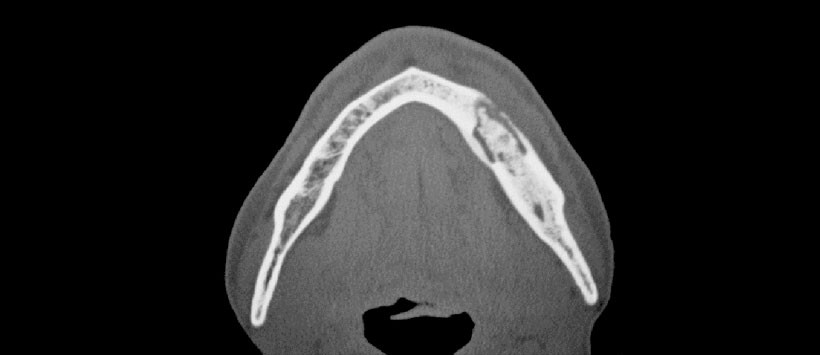

Figura 2: La tomografía volumétrica, es el examen ideal para la evaluación precisa de la osteonecrosis, nos indica la cantidad de secuestros óseos y la extensión de la lesión. En la figura se muestra una osteonecrosis mandibular ocasionando una hipoestesia del mentón.